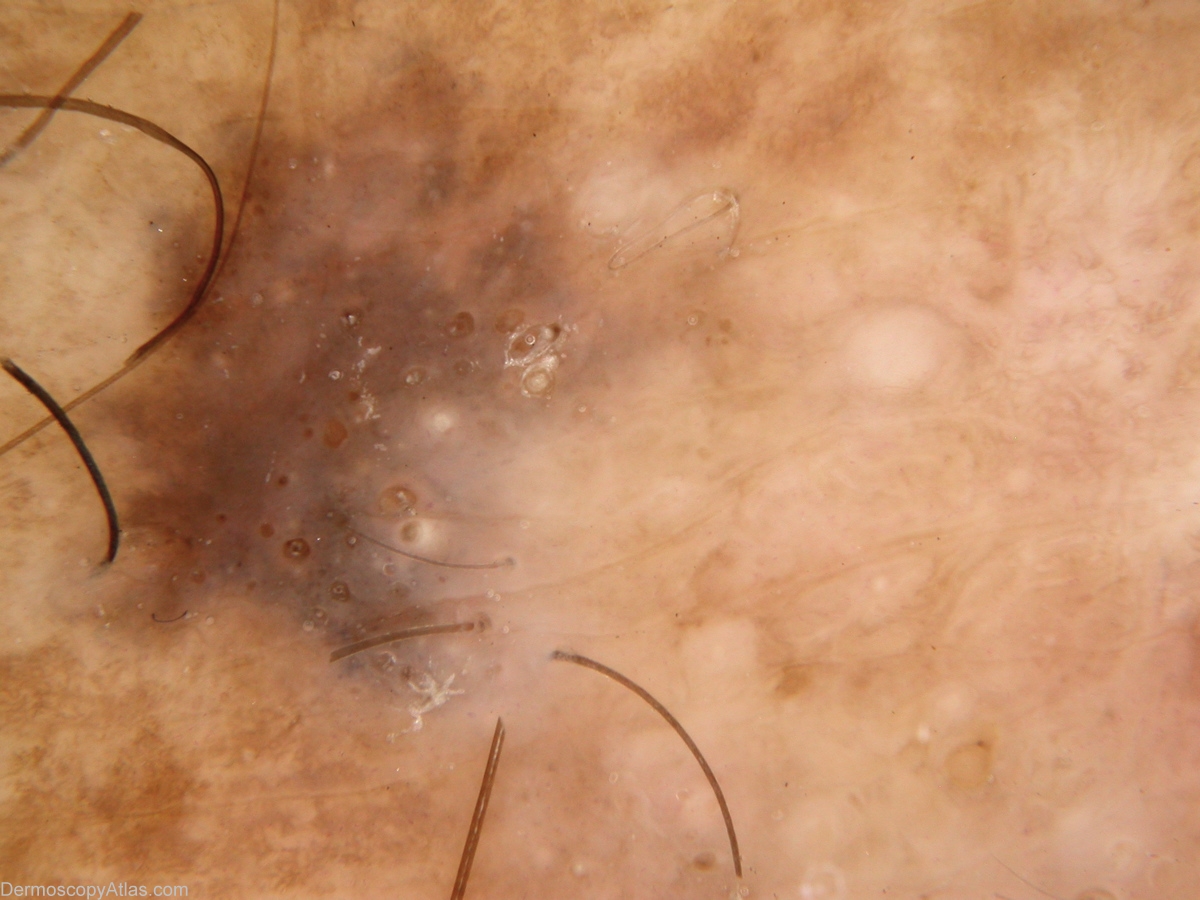

Site: Calf

Diagnosis: Seborrhoeic keratosis

Description: Extensive regression (white area) raises suspicion clinically. Comedo-like openings best seen in detail view define this as seborrheoic keratosis